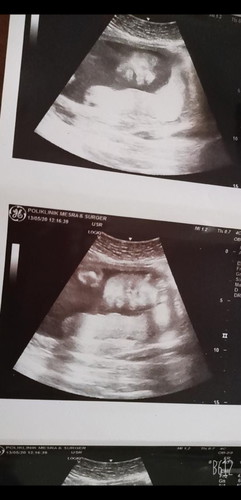

Hri nie 24weeks tdi pi scan bby semua okey....#1 je masalah bby songsang TakuT pula sebap Bby frist D sna sape ad pegalaman cm sy nie bby akan bepusing ke lage